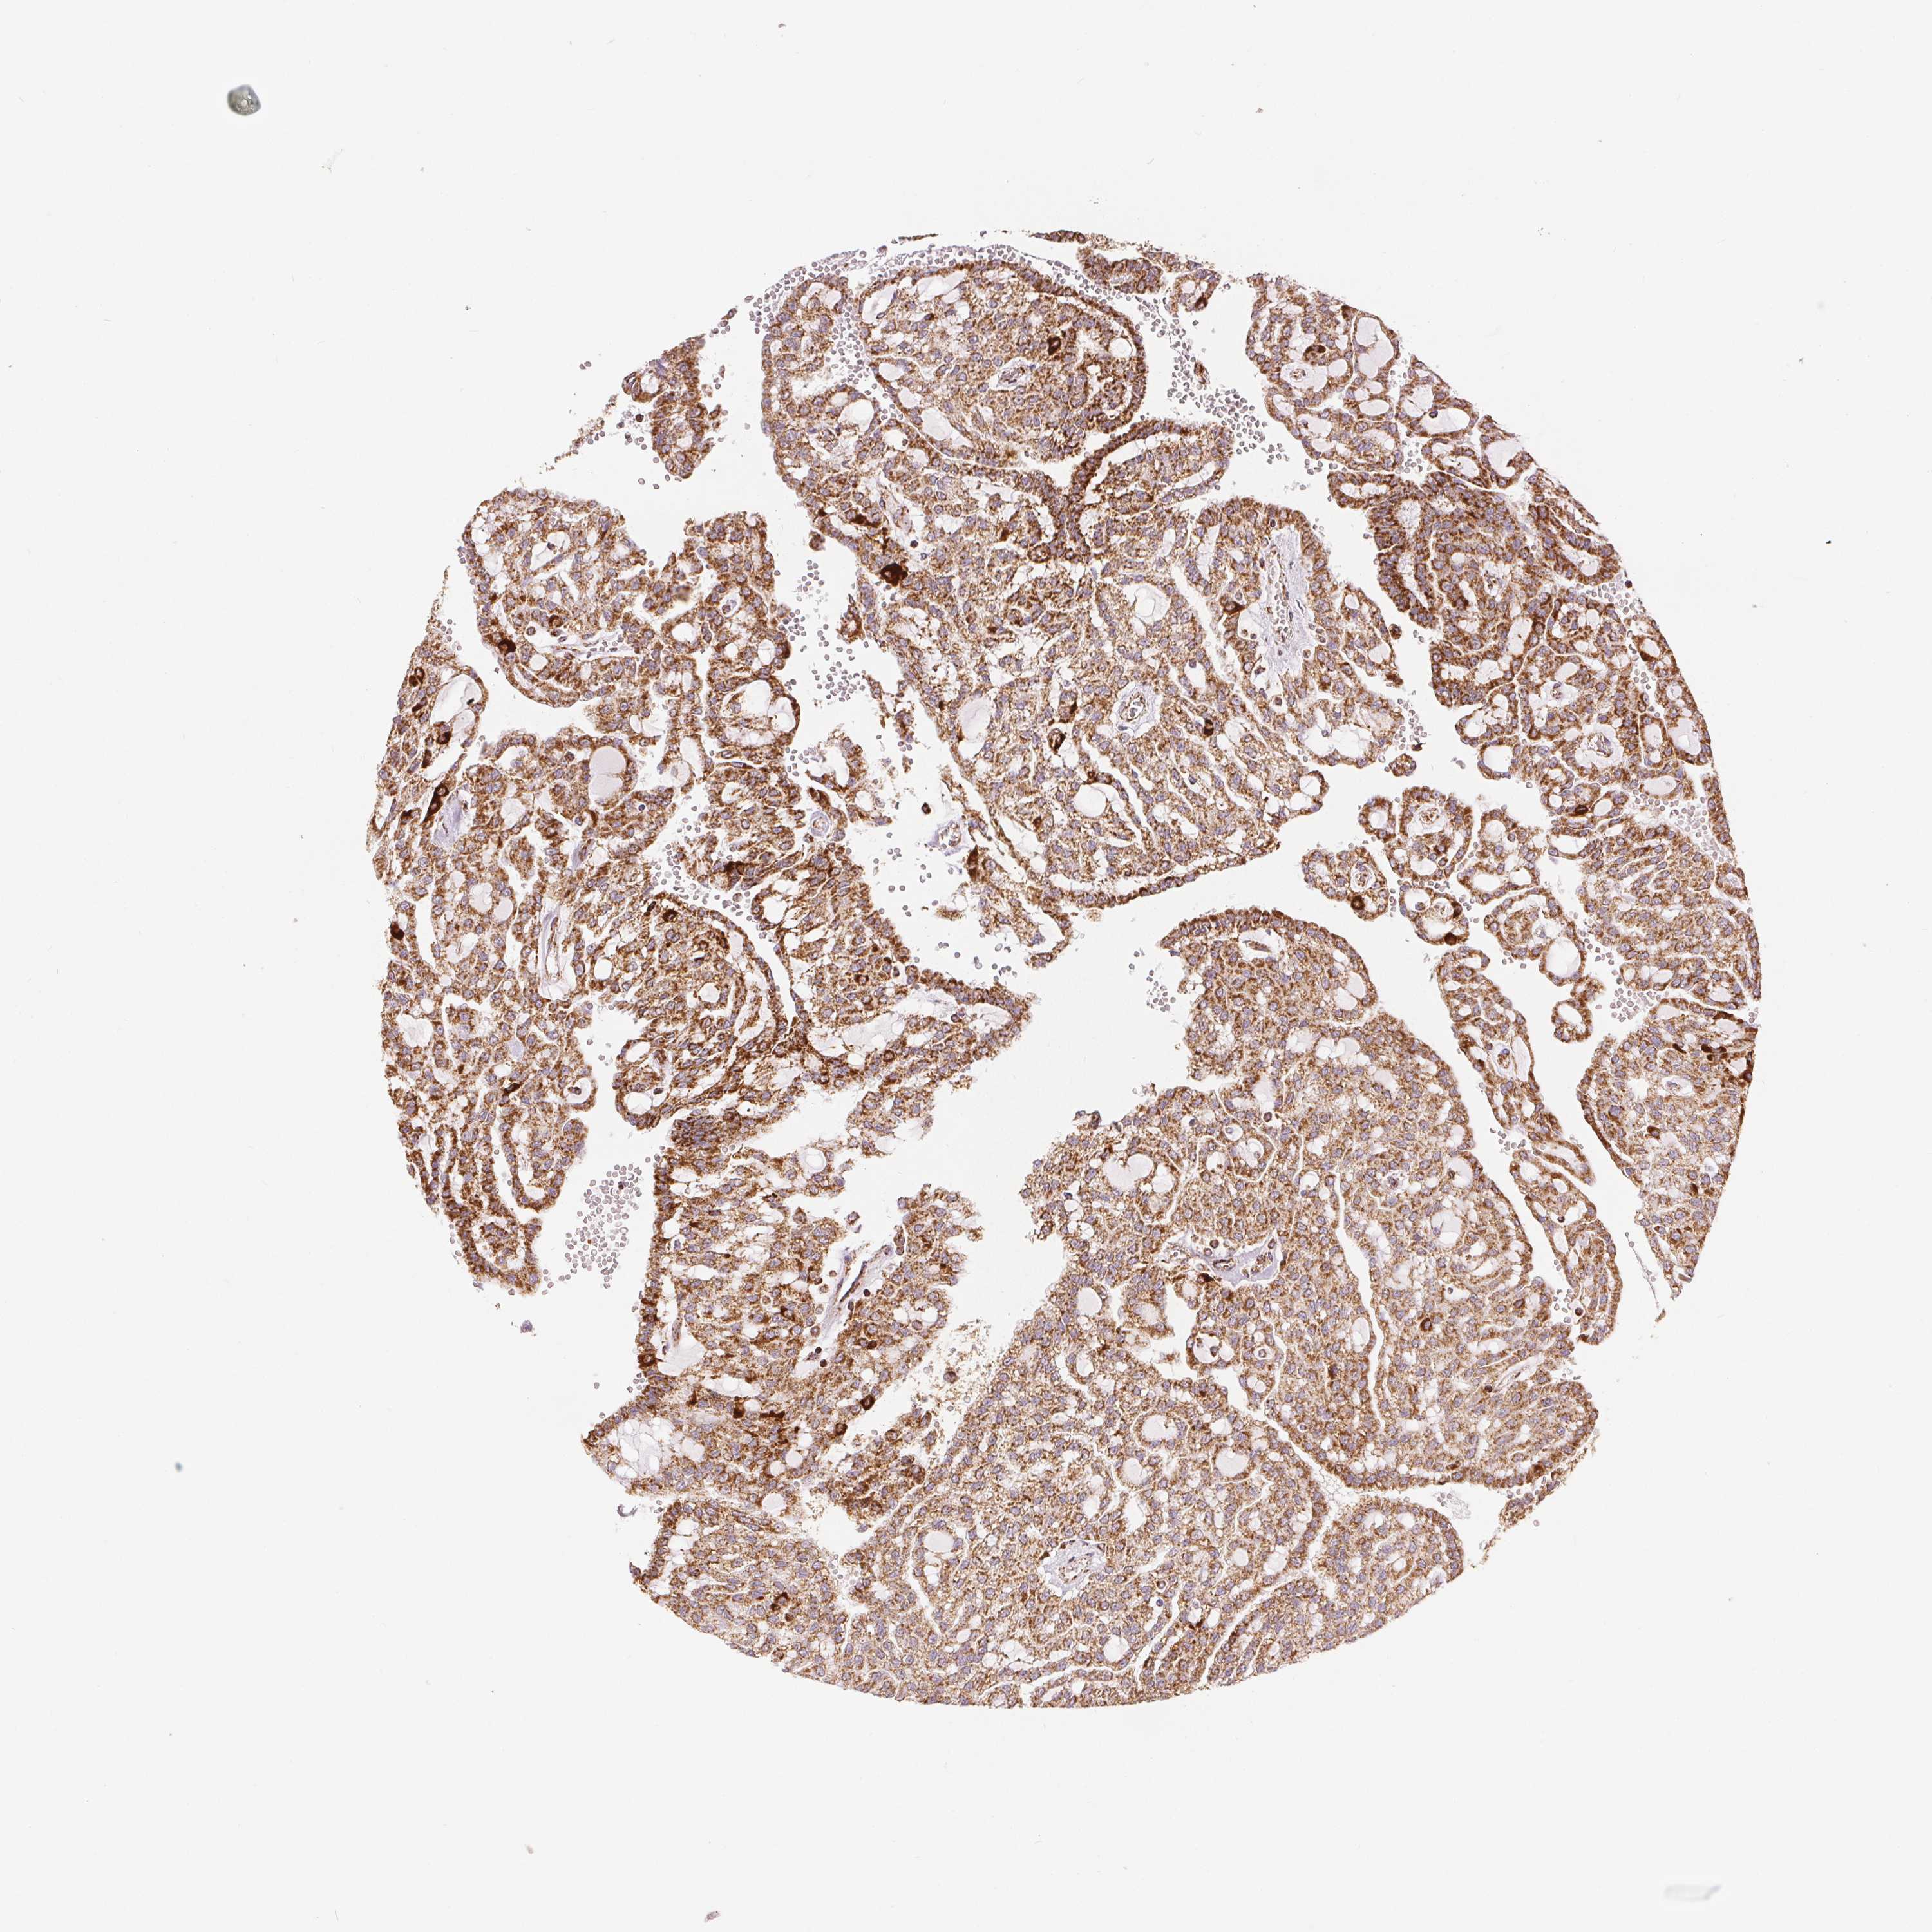

CANCER RENAL CANCER Show tissue menu

KICH TCGA KIRC TCGA KIRC VALIDATION KIRP TCGA PROTEIN RCC CPTAC PROTEIN EXPRESSION